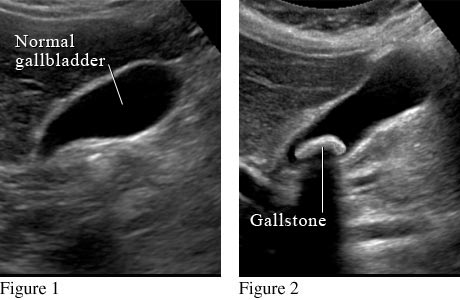

The most common test is an abdominal ultrasound. A technologist moves a wand across your belly to create pictures on a screen. Blood tests may be done to find out if gallstones are causing other serious problems or if your symptoms are caused by something else.

What a gallstone looks like on an abdominal ultrasound

Courtesy of Intermountain Medical Imaging, Boise, Idaho.

Figure 1 shows a normal gallbladder on ultrasound. Figure 2 shows a large gallstone in the gallbladder.